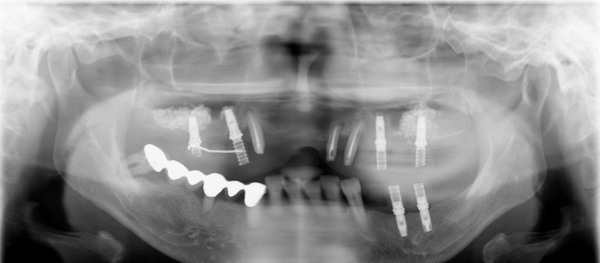

上顎奥歯のインプラント治療はサイナスリフト(骨造成)をおこないました。

治療後

重度の歯周病で咬み合わせがなくなった治療は、歯周病の治療やインプラントを埋入するだけではなく、咬合診断をおこない咬合再構成が必要になってきます。